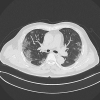

Clinical, laboratory, and computed tomography (CT) findings of 5 cases of the novel Coronavirus Disease 2019 (COVID-19) pneumonia from patients outside of Wuhan were reviewed. The human-to-human transmission of the virus may explain the infection of the disease outside of Wuhan. CT examination is important in the early detection and follow-up of the disease. With a history of exposure or travelling, symptoms of fever and cough, and the typical CT manifestation such as ground-glass opacity with a peripheral distribution, we should also think of the possibility of the COVID-19 pneumonia in patients outside of Wuhan.